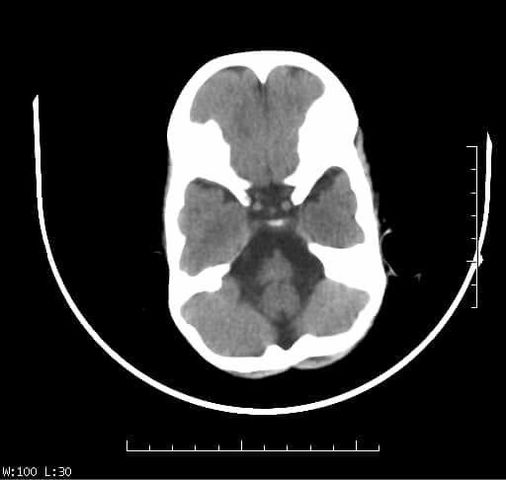

• conceptualización por areas y por lóbulos: areas primarias de codificación y de recepción inical de la información, las areas de asociacion secundaria y areas de asociacion terciaria donde se hacen asociaciones intermodales y polimodales. :